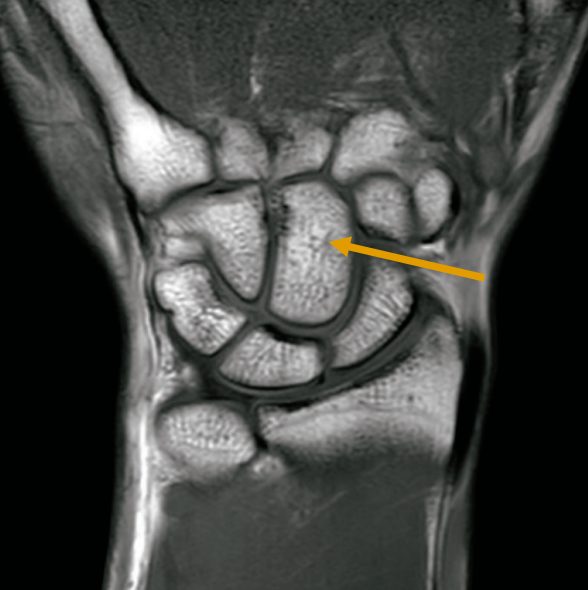

24 手部MRI のT1強調冠状断像を示す。矢印で示すのはどれか。

1.月状骨

2.舟状骨

3.有鉤骨

4.有頭骨

5.小菱形骨

手の骨の問題2問目

あと1問ある

今年は本当に問題かぶりが多い